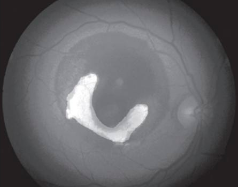

• Although the choroid is better assessed using ICGA, early lacy hyperfluorescence may be seen on IVFA. It represents subretinal neovascularization.

• The differential for subretinal neovascularization includes: retinochoroidal tumours, choroidal tumours, exudative macular degeneration, angioid streaks, histoplasmosis, myopia and choroidal rupture.